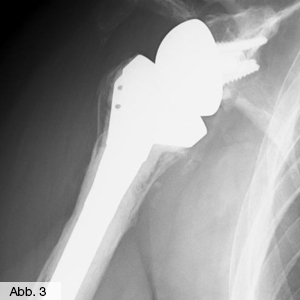

Der aus dem Griechischen stammende Begriff Endoprothetik bedeutet so viel wie "innerer Ersatz" und umschreibt in der Medizin die Möglichkeit, ein krankhaft oder unfallbedingt verändertes Gelenk durch ein künstliches Implantat zu ersetzen. In der Orthopädie kommt der Gelenkersatz vorwiegend bei fortgeschrittenem Verschleiß der Gelenke wie beispielsweise Hüfte (Abb. 1), Knie (Abb. 2), Schulter (Abb. 3) oder Ellenbogen zum Einsatz. Wenn im Falle einer so genannten Arthrose konservative Maßnahmen nicht zur gewünschten Schmerzlinderung führen, ist eine gelenkersetzende Operation für den Patienten in der Regel unausweichlich. Dass hierbei höchste Präzision und Patientensicherheit an oberster Stelle stehen, bestätigt die im Jahr 2014 erfolgte Zertifizierung zum EndoProthetikZentrum der Maximalversorgung.

Bild Orthopädie Schulterinversprothese

• spezielle Schulterendoprothetik (bei kompletter Zerstörung der gelenkübergreifenden Muskulatur)